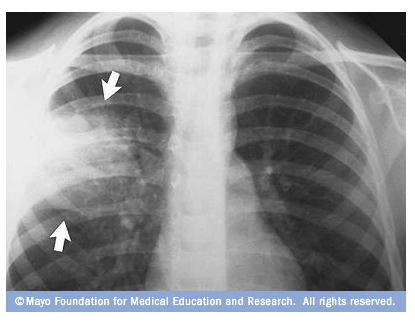

A chest x-ray may show area of inflammation, similar to the image above, which is a clear indicator of pneumonia. This indicator would lead to a diagnosis, and recommendation for a medical remedy. The question posed here is: Could an Artificial Neural Network perform this diagnostic task from an x-ray image? If so, how well could it perform?